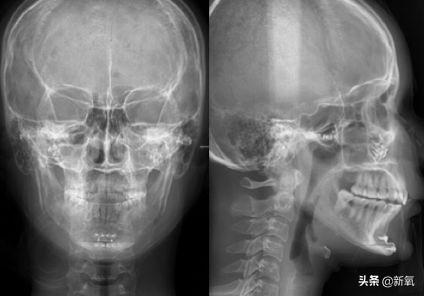

这次赴韩整形是Jenny人生中第六次整形手术,也是有史以来大的一次手术。她一次性做了三个大项目:第四次假体隆鼻、颧骨内推,以及激光溶脂。

2015年9月,在更了解自家代理的医院和医生后,Jenny做了第二次轮廓手术,包括第二次颧骨手术、取出下巴的硅胶假体,以及V-line轮廓手术...

Vline手术的部分是把她的下巴切成T型,去掉中间的一部分骨头,再修剪骨头边缘,主要目的就是让脸小一点...

因为Jenny没有下巴,所以就在以上步骤的基础上,又把下巴再往前移动了一点,后用钛钉固定。